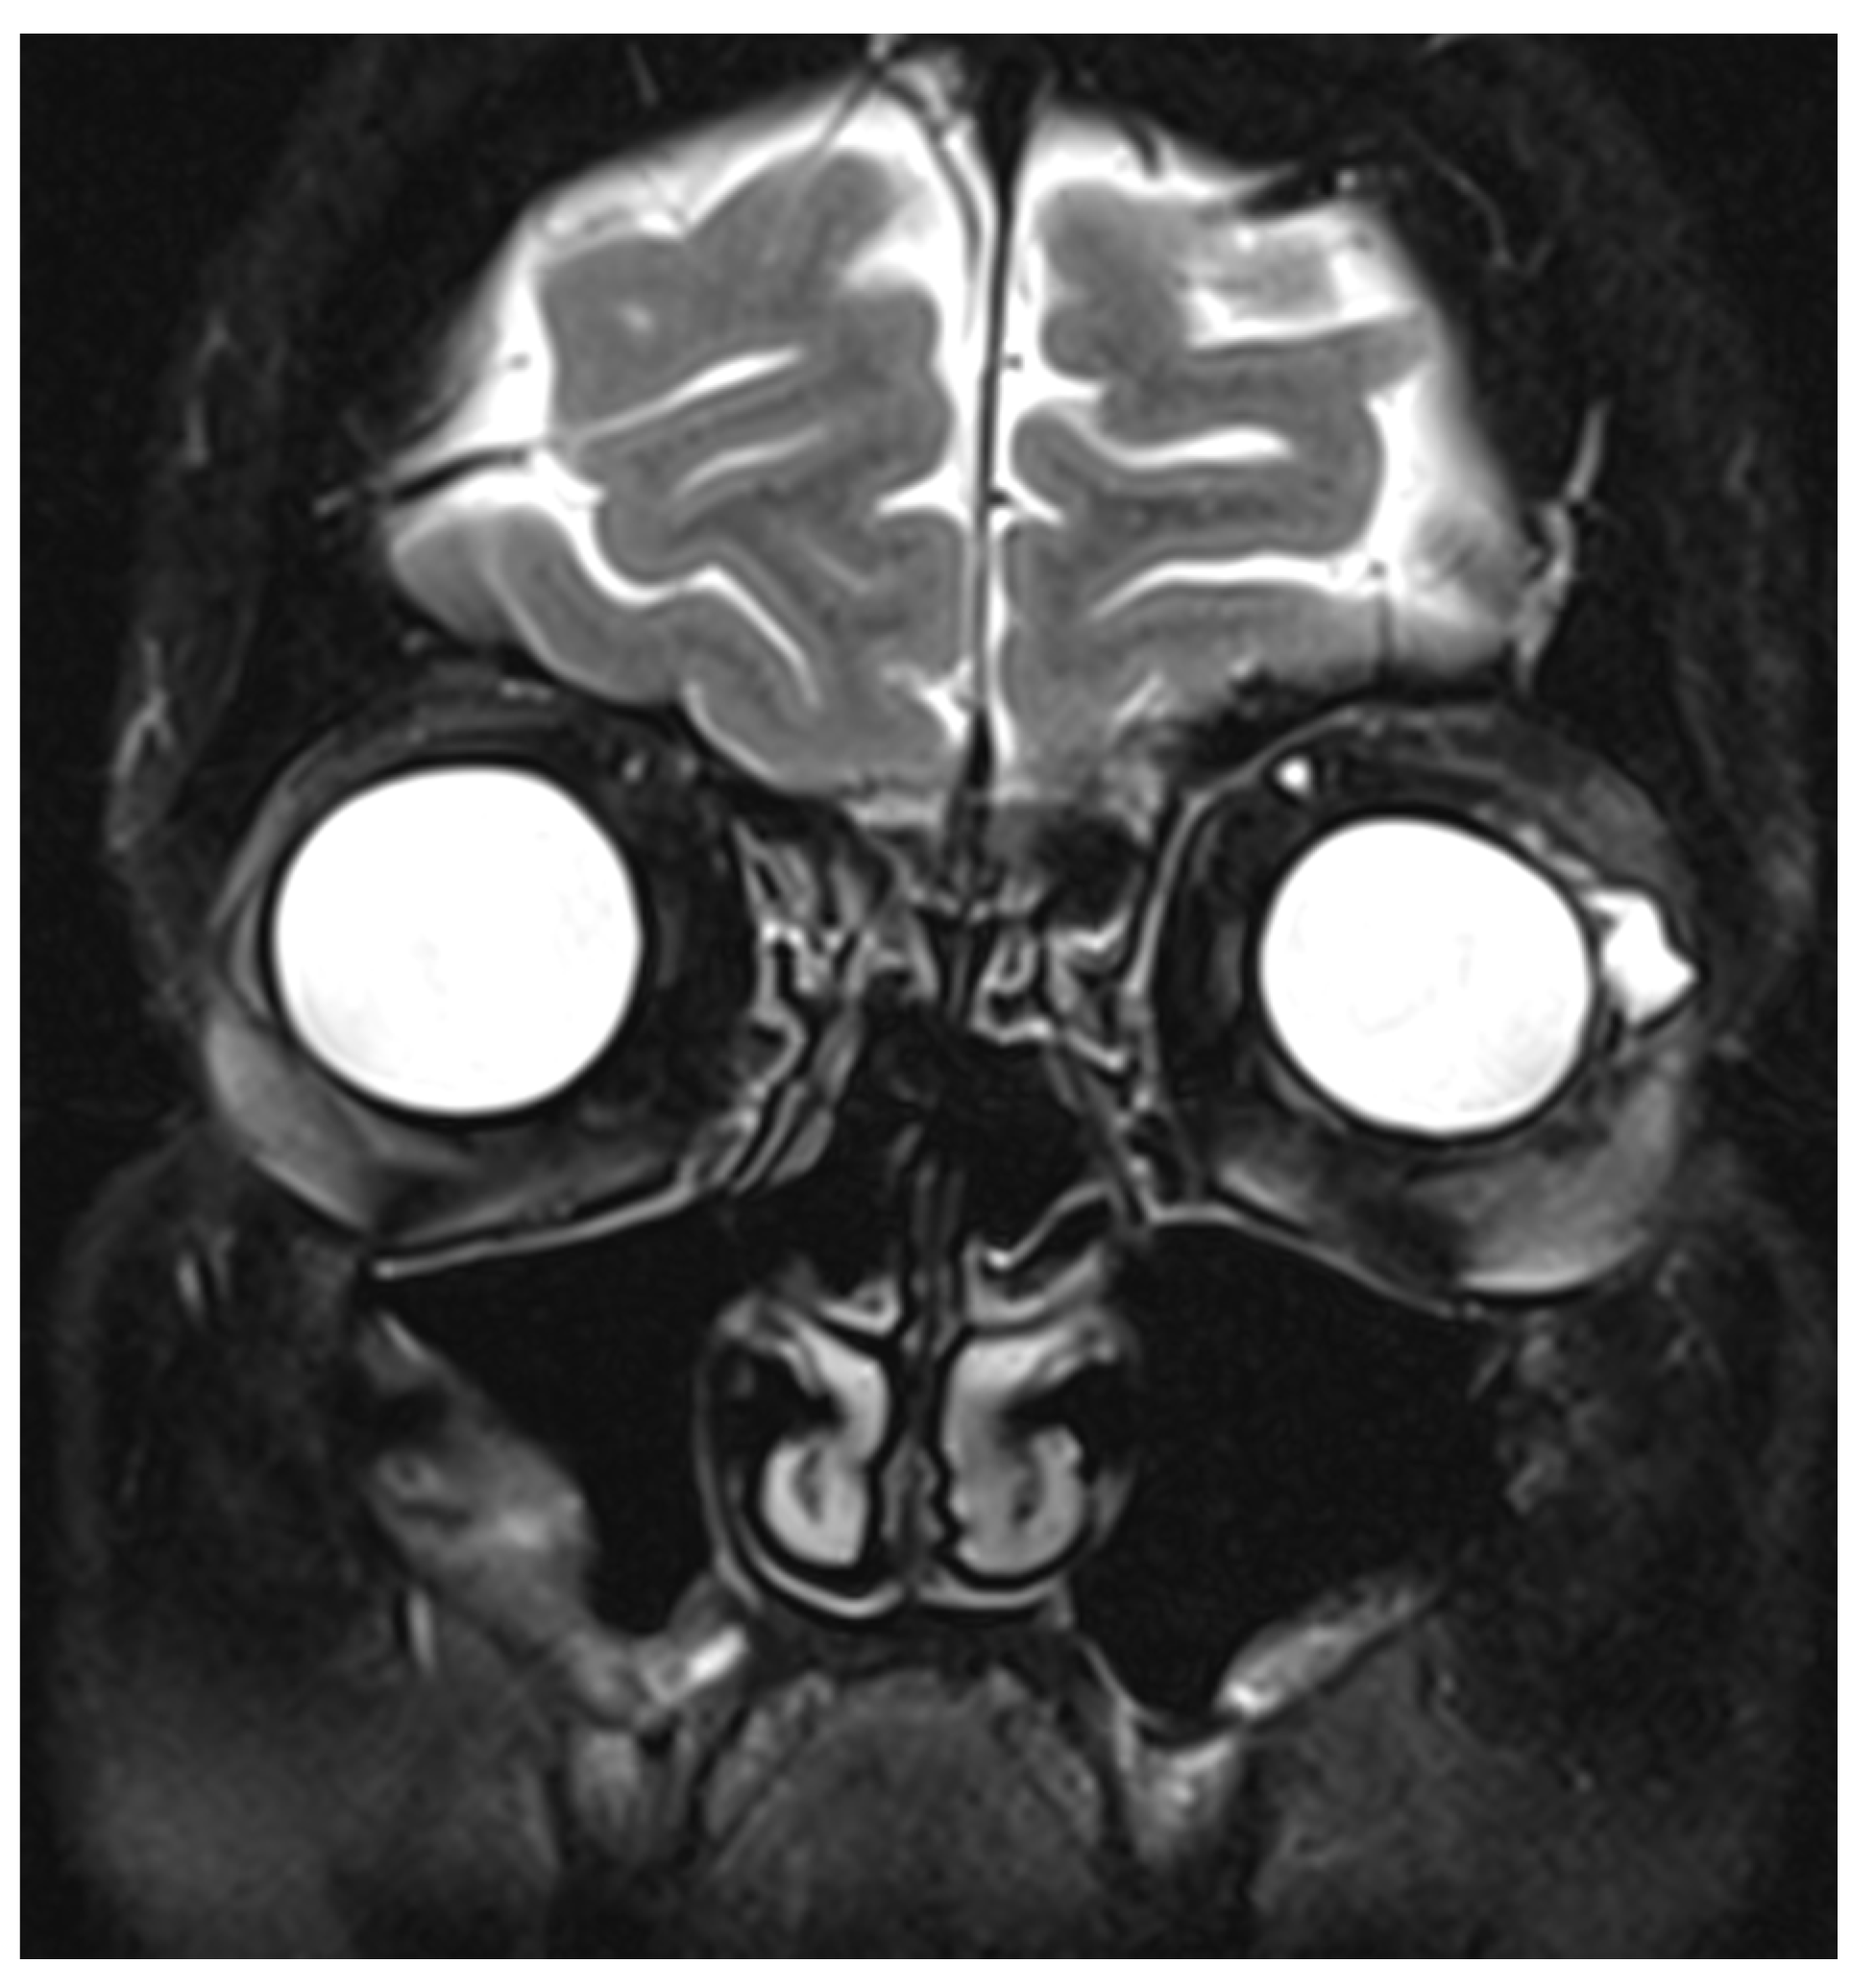

Figure 4.

Coronal section of T2-weighted sequence of magnetic resonance imaging (MRI) of the orbits showing a cystic elevation above the left lateral rectus, likely to be a remnant of exposed hydrogel explant.